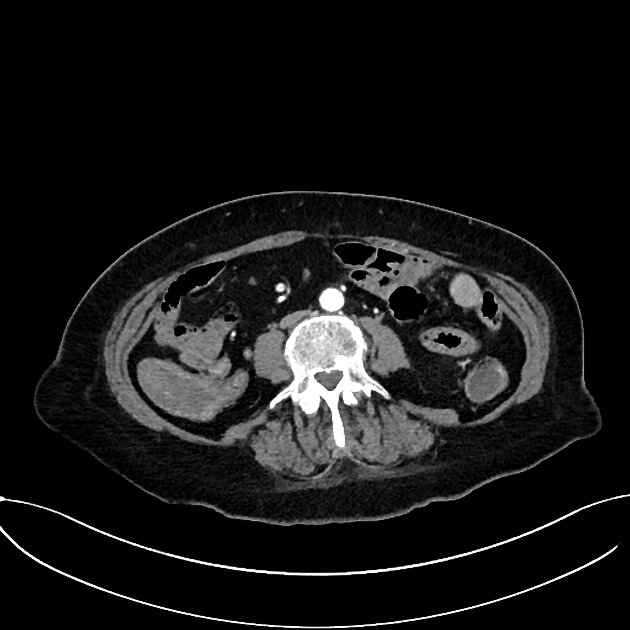

Axial C+delayed

Axial C+ arterial phase